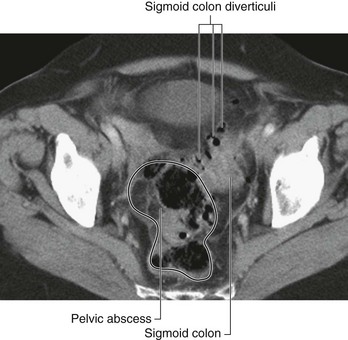

Page 392

Blood from the lower limbs and the pelvis may drain via a series of collateral vessels, some of which include the superficial inferior epigastric veins, which run in the superficial fascia. These anastomose with the superior, superficial, and deep epigastric venous systems to drain into the internal thoracic veins, which in turn drain into the brachiocephalic veins and the superior vena cava.

After the initial inferior vena cava thrombosis, the veins of the anterior abdominal wall and other collateral pathways hypertrophy to accommodate the increase in blood flow.

Case 3 LIVER BIOPSY IN PATIENTS WITH SUSPECTED LIVER CIRRHOSIS